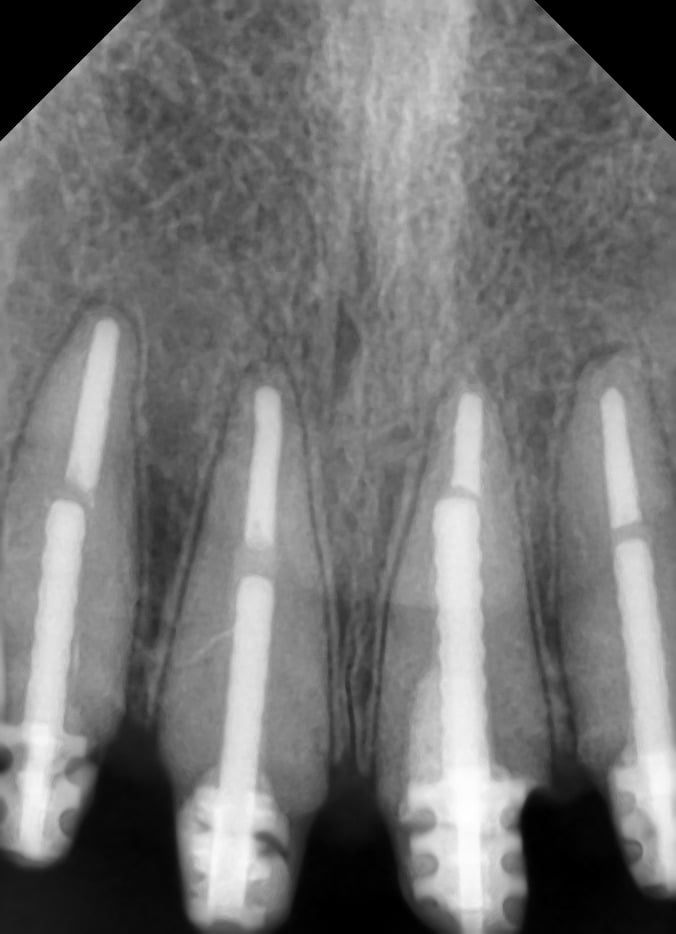

intraoral examination, root remnants 12,11,21&22.

radiologic examination showed root length of 19mm for central incisors and 18mm for lateral incisors.

endodontic treatment was done, core buildup with dentisply metal post placed with glass ionomer cement, (fuji.). Joined ceramic crowns 12&11, 21&22 (ivoclar IPS eMax press LT A2) was done.